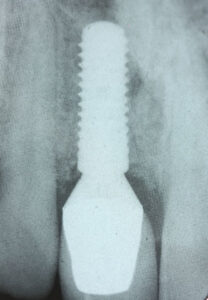

At Pearl Dental Clinic, we understand the significance of a healthy, confident smile. Dental implant treatments are surgical procedures that replace teeth with metal screw posts with a crown on top. They look and function pretty much like real ones. This is why they are a popular and effective solution for those seeking a permanent replacement for their missing teeth. We are dedicated to providing high-quality dental implants (only the best brands) at a competitive cost. Thus, we do our best to ensure everyone can access the transformative benefits of this life-changing treatment.

Dental implants not only restore your smile but also enhance your overall oral health. Unlike dentures, implants are a permanent solution, designed to fuse with your jawbone, providing unparalleled stability and functionality. They look and feel like natural teeth, allowing you to eat, speak, and smile with confidence.

Several factors influence the cost of dental implants, including the number of implants needed, the type of implant, and any additional procedures required, such as bone grafting or sinus lifts. Rest assured, our team will discuss all aspects of your treatment plan to ascertain that you have a comprehensive understanding of the costs involved. Only then will we ask you to proceed.